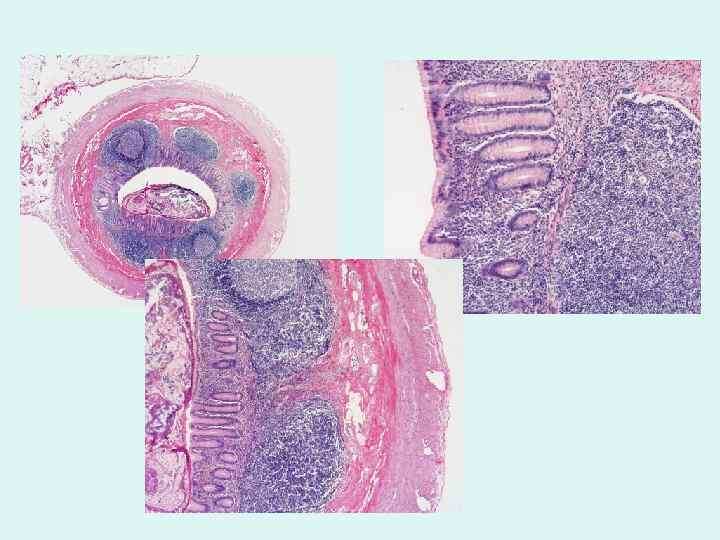

4. Эндоскопия – ключевой метод!

Колоноскопия:

Позволяет осмотреть толстую кишку и конечный отдел тонкой (подвздошную). Ищем специфические изменения:

Язвы (часто поперечные, «опоясывающие»)

Полиповидные образования

Стриктуры (сужения)

Свищи

Биопсия! ⭐️ САМОЕ ВАЖНОЕ! Берем кусочек измененной ткани во время колоноскопии. Гистологическое исследование ищет:

Гранулёмы (характерные скопления клеток) с казеозным некрозом (творожистый распад в центре – очень подозрительно на ТБ!).

Кислотоустойчивые бактерии (КУБ) при специальной окраске.